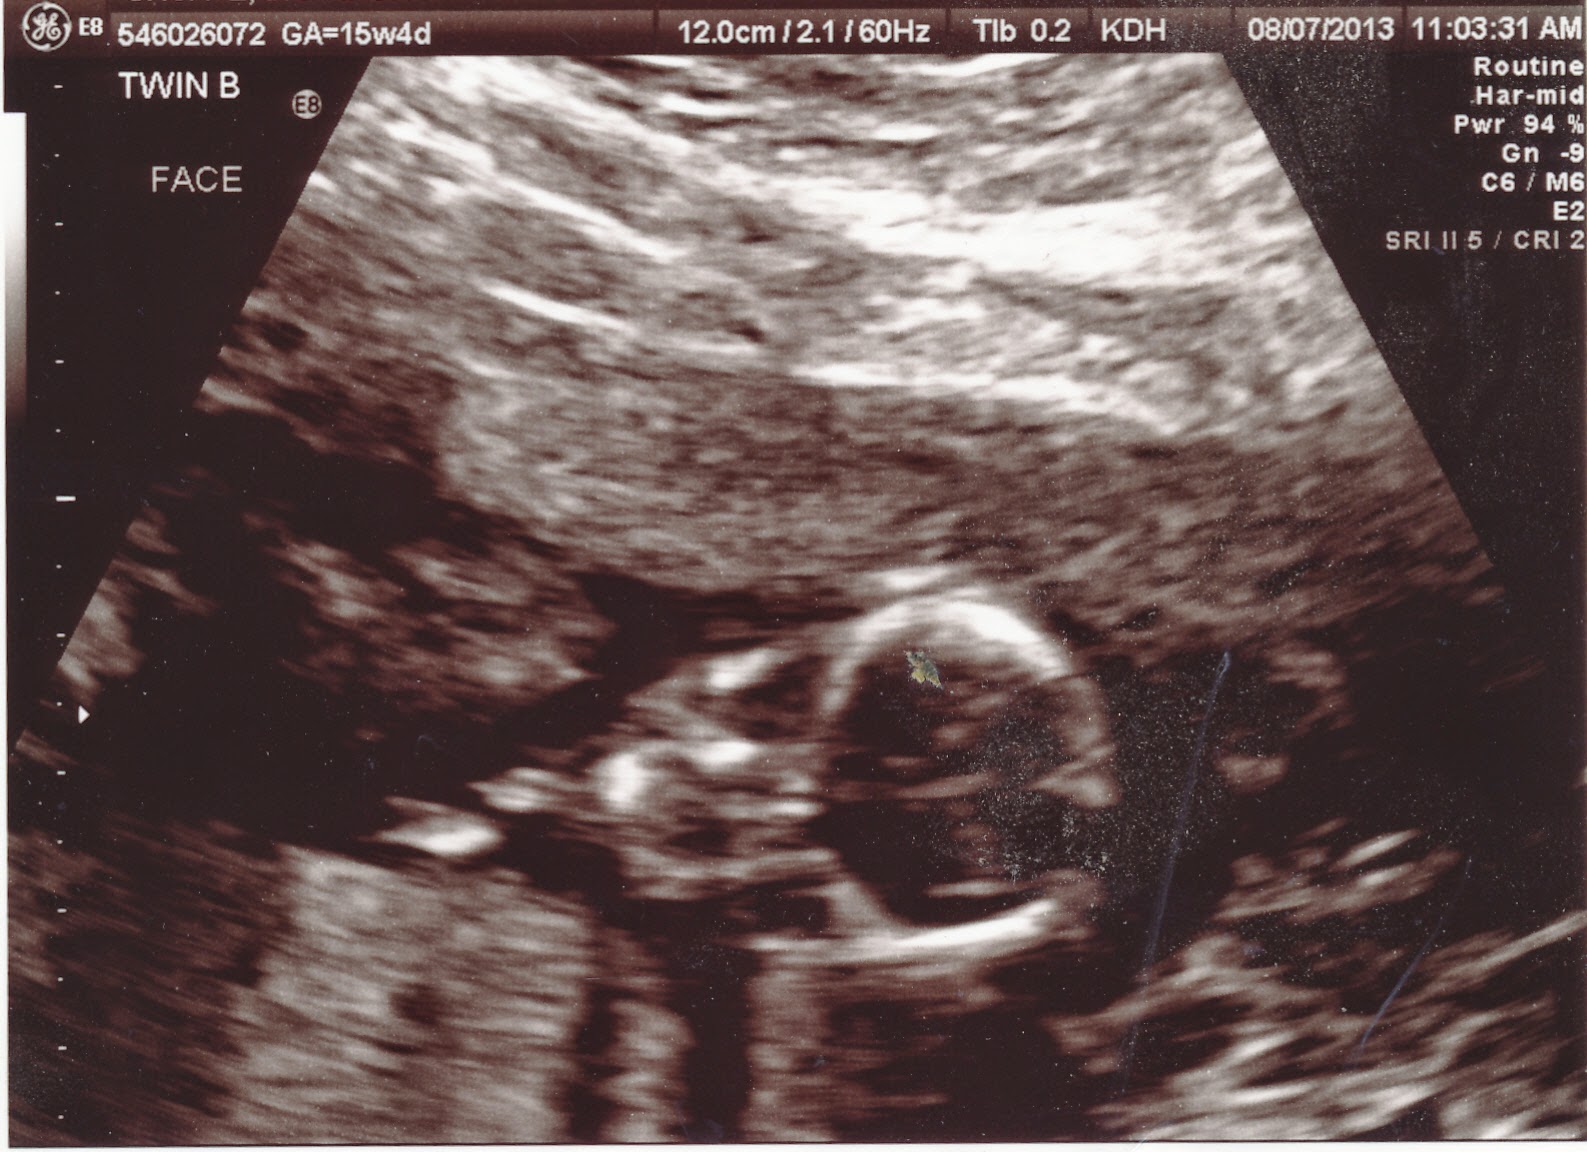

The day before I was to be 23 weeks pregnant I had my last appointment with the doctor. She told me it is normal for PPROM women not to bond with the babies they think might die. It was hard coping during this time knowing that I had done everything right and yet still there was nothing I could do to save them. It was out of my hands now. I had my last ultrasound to check how big the babies were in case I would be delivering soon.

Baby A

Baby B